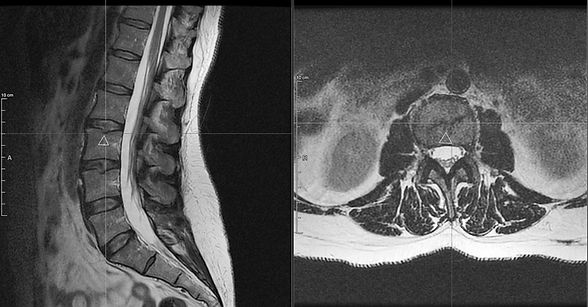

That’s why so many people have “abnormal” MRIs and no pain — like the image of one of our successful student-patient, to the left — and others have severe pain with relatively mild imaging findings — like the image below (also another successful student-patient!)